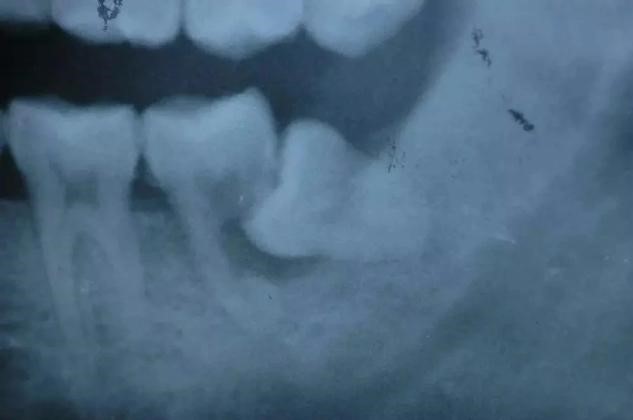

2、磨牙龋齿:对于向前倾斜的阻生智齿,食物通常积聚在相邻牙齿之间,这容易导致相邻牙齿(下第二磨牙)的龋齿。这种龋齿不容易被发现,一旦出现疼痛(急性牙髓炎),牙冠通常会严重受损。出现龋齿、牙髓炎,甚至牙齿不能保留。第二磨牙缺失对咀嚼功能有很大影响,也很难用义齿修复。

3、骨髓炎。冠周炎或龋齿很容易导致根周炎,感染比较严重时,炎症还可能会向牙髓腔周围扩散,从而引发牙髓炎,除了出现剧烈疼痛等明显症状外,还可能导致出现牙齿松动。